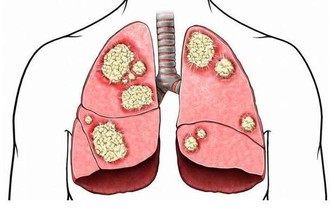

長期如此,不僅容易導致腹脹、胃痛,還可能引起胃潰瘍、反流性胃炎、食道炎等胃腸疾病,甚至可能引發胃癌。

幽門螺桿菌主要潛伏在胃粘膜組織中,人一旦感染這種細菌,就可能引起口臭、胃炎,甚至是胃癌。